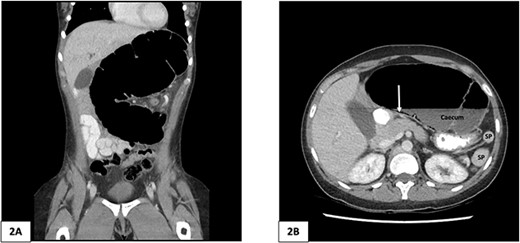

Computed tomography of the abdomen and pelvis of 25-year-old female patient. (A) Coronal slice demonstrating caecal volvulus with distended loop of colon. (B) Axial slice demonstrating 97 mm diameter distended caecum, multiple splenic fragments, arrow indicates pneumatosis coli, indicating colonic ischaemia. SP, spleen fragments.

There was malrotation of the gut with all colon on the left side and most of the small bowel on the right side of the abdomen (Fig. 2A). There was duplication of the infrarenal IVC, interruption of the suprarenal IVC with azygos continuation (Fig. 1C–F). A left-sided IVC draining venous blood from the left common iliac vein was present which drained into the left renal vein, while the right IVC drained blood from the right common iliac vein into the right renal vein. A retroaortic communication draining blood from the right IVC into the left IVC was also noted. From the renal veins all venous return was via the azygos vein to the superior vena cava with interruption of the suprarenal IVC. A suprahepatic IVC draining blood from the middle, left, and right hepatic veins into the right atrium was present (Fig. 1B). The spleen was divided into five distinct fragments, all within the splenic fossa and each supplied by an individual branch of the splenic artery (Figs 1 and 2).

A plain abdominal X-ray was performed showing a grossly distended loop of colon in the left upper abdomen. Subsequent computed tomography (CT) scan of the abdomen and pelvis was obtained using oral and intravenous contrast with images acquired during portal venous phase. The CT showed a mesenteric whirl sign (Fig. 1A) and caecal volvulus with the caecum measuring 97 mm diameter at its most distended point with associated pneumatosis coli (Fig. 2A and B).